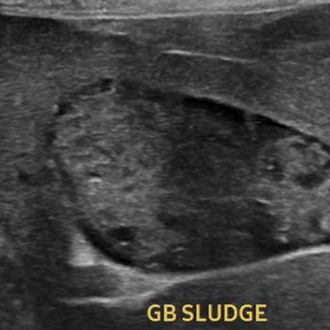

담낭점액낭종 수술

담낭에 점액이 비정상적으로 쌓여 염증이나 파열 위험이 커지는 경우에 시행하는 수술입니다.

상태에 따라 담낭을 제거해 합병증을 예방합니다.